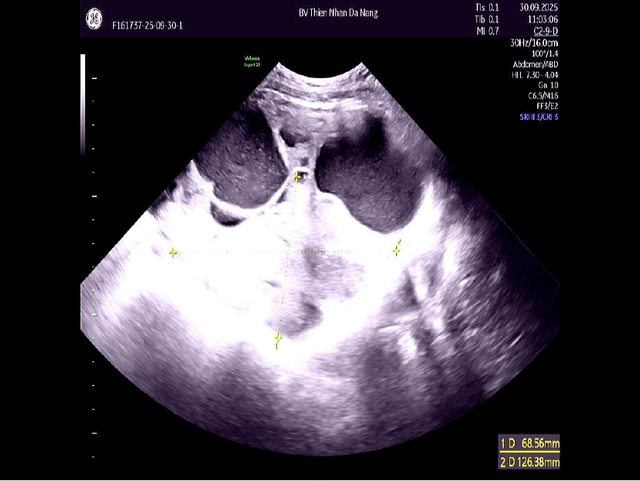

Đến cuối tháng 9/2025, khi xuất hiện đau bụng, chướng vùng rốn và ra huyết âm đạo kéo dài, chị T. đến Thiện Nhân Hospital thăm khám. Kết quả siêu âm ghi nhận khối u phát triển nhanh, kích thước 16–17 cm, chiếm gần trọn ổ bụng, tương đương với thai khoảng 6 tháng.

Kết quả siêu âm